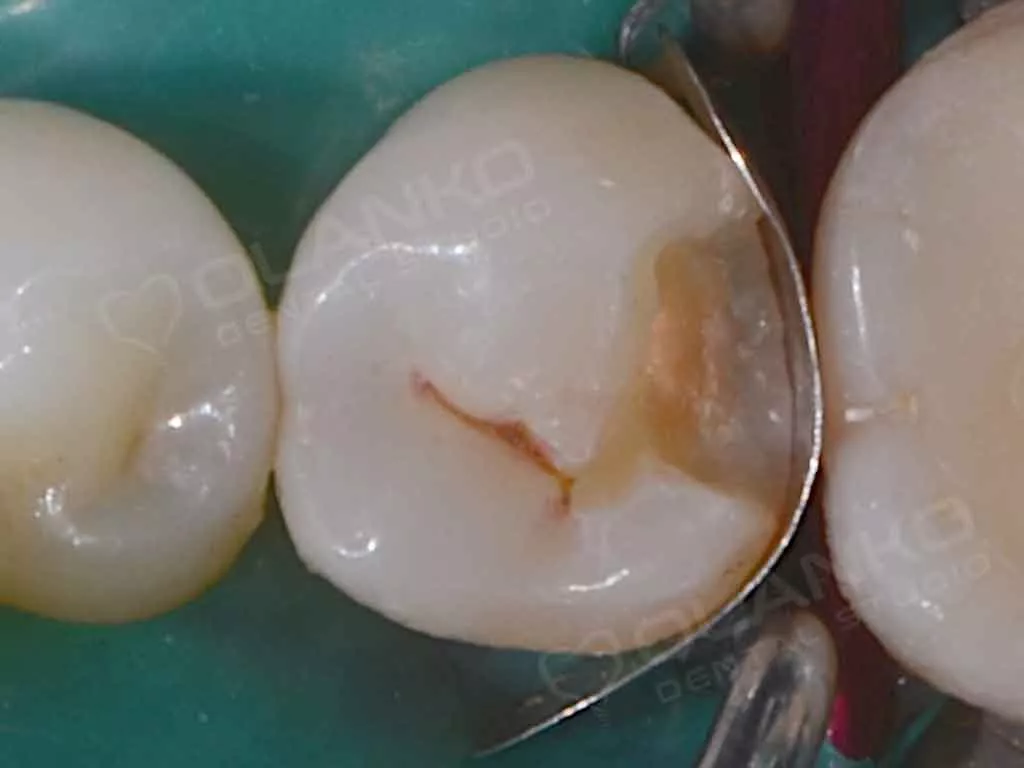

Фото до начала лечения, кариозная полость на боковой поверхности зуба